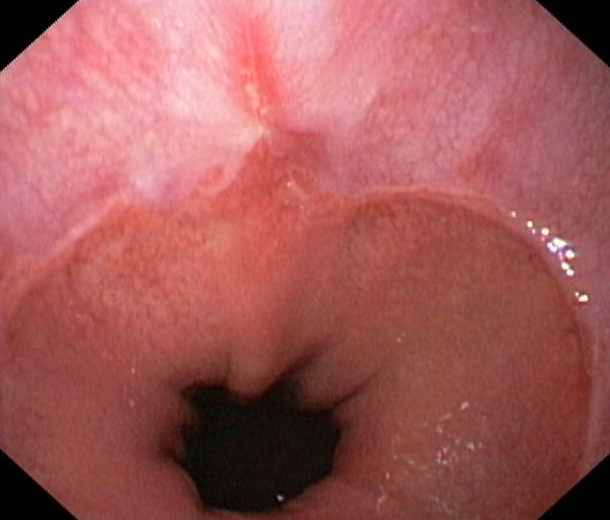

Stomach:

Hyperplastic polyps